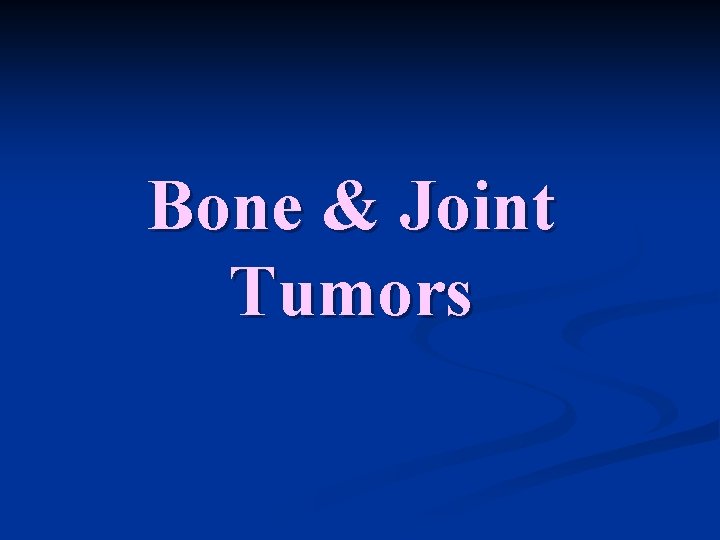

Bone Joint Tumors Periostal reactions Response to RAPIDLY

Bone & Joint Tumors